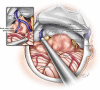

Glioblastomas presenting topographically at the cerebellopontine angle (CPA) are exceedingly rare. Given the specific anatomical considerations and their rarity, overall survival (OS) and management are not discussed in detail. The authors performed an integrative survival analysis of CPA glioblastomas. A literature search of PubMed, Scopus, and Web of Science databases was performed per PRISMA guidelines. Patient data including demographics, clinical features, neuroimaging, management, follow-up, and OS were extracted. The mean age was 39 ± 26.2 years. The mean OS was 8.9 months. Kaplan-Meier log-rank test and univariate Cox proportional-hazards model identified hydrocephalus (log-rank, p = 0.034; HR 0.34; 95% CI 0.12-0.94; p = 0.038), chemotherapy (log-rank, p < 0.005; HR 5.66; 95% CI 1.53-20.88; p = 0.009), and radiotherapy (log-rank, p < 0.0001; HR 12.01; 95% CI 3.44-41.89; p < 0.001) as factors influencing OS. Hydrocephalus (HR 3.57; 95% CI 1.07-11.1; p = 0.038) and no adjuvant radiotherapy (HR 0.12; 95% CI 0.02-0.59; p < 0.01) remained prognostic on multivariable analysis with fourfold and twofold higher risk for the time-related onset of death, respectively. This should be considered when assessing the risk-to-benefit ratio for patients undergoing surgery for CPA glioblastoma.